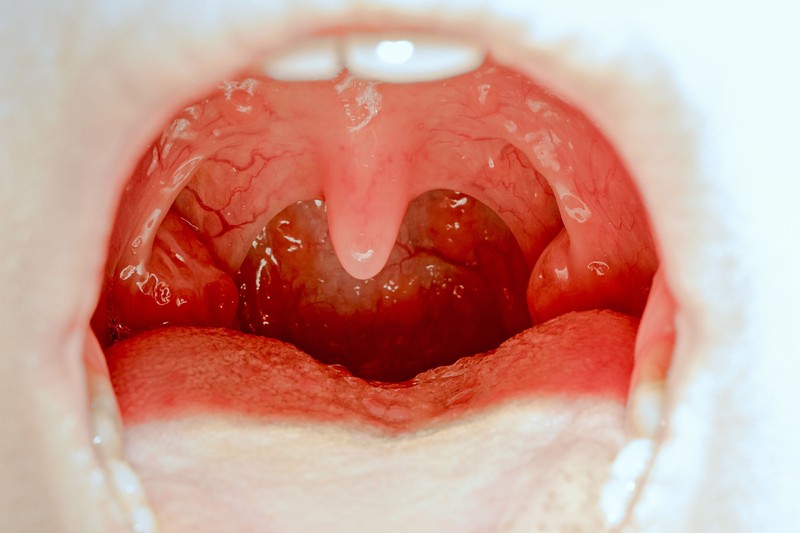

Mandulagyulladás

Gyerekkorban gyakran okoznak panaszokat az orr és a garatmandulák. Hol a gyulladás, hol csupán a méretük a probléma alapja.

A torokfájás, főleg gyerekkorban a mandulák gyulladásával is járhat. Így kezelhető!

Az orrmandula megnagyobbodása sok panaszt okozhat gyermekkorban, ezek egyike a halláscsökkenés.